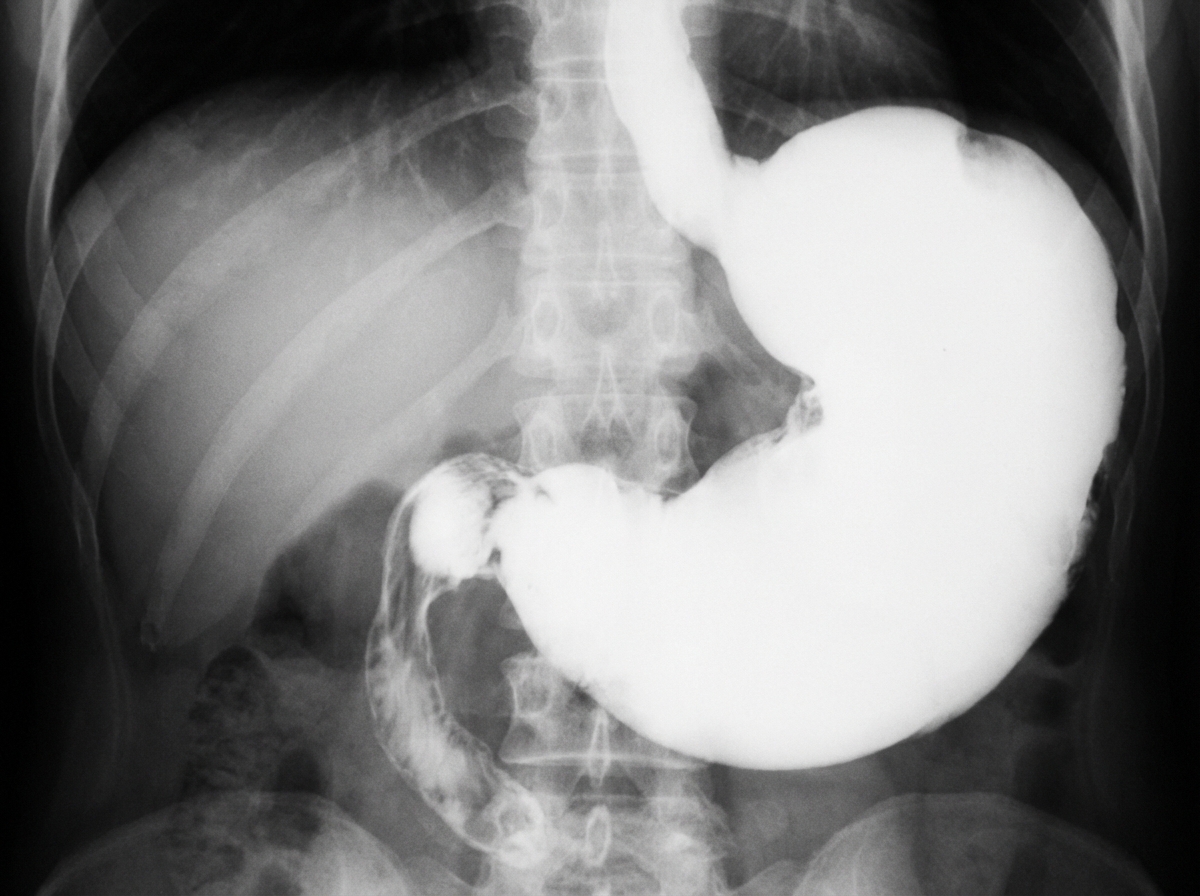

Which is the most common cause of the below condition?

Explanation: ***Gastric carcinoma*** - **Antral carcinoma** is the most common cause of **gastric outlet obstruction** in adults, causing pyloric stenosis through tumor growth and fibrosis. - Typically presents with **progressive dysphagia**, **weight loss**, and **epigastric pain** with a palpable mass. *Gastric ulcer* - Gastric ulcers rarely cause **pyloric stenosis** as they typically occur in the body or fundus, not near the pylorus. - When they do occur near the pylorus, they more commonly cause **perforation** or **bleeding** rather than obstruction. *Duodenal ulcer* - Can cause **pyloroduodenal obstruction** through scarring and fibrosis, but is **less common** than gastric carcinoma as a cause of gastric outlet obstruction. - Usually associated with **H. pylori infection** and presents with **postprandial pain** rather than progressive obstruction. *Hiatus hernia* - Involves **herniation of stomach** through the **diaphragmatic hiatus** into the thoracic cavity. - Does **not cause pyloric stenosis** as it affects the gastroesophageal junction, not the gastric outlet.